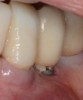

Whether or not to probe around dental implants has been a topic of debate in the dental community for years. Recent consensus supports periodic probing around dental implants so that changes in probing, such as the presence of bleeding on probing, suppuration, and probing depth, can be identified over time.5 If bleeding on probing is present, then the cause(s) of this bleeding should be identified and a proactive treatment approach taken before bone loss begins to occur around the implant. Bleeding may result from poor oral hygiene or a lack of adequate keratinized tissue around the implant (Figure 2). And insufficient keratinized tissue in the presence of poor oral hygiene may lead to an even greater level of peri-implantitis.6 This can result in increases in gingival bleeding, plaque index, pocket depth, and bleeding on probing. Therefore, the presence of adequate thickness and keratinization of soft tissue around dental implants is a necessity.